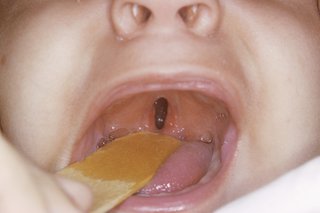

Rozszczep podniebienia może być po prostu otworem w tylnej części jamy ustnej lub pęknięciem w podniebieniu, które biegnie aż do przedniej części jamy ustnej.

MORRIS HUBERLAND / SCIENCE PHOTO LIBRARY

Czasami może być ukryty przez wyściółkę podniebienia.